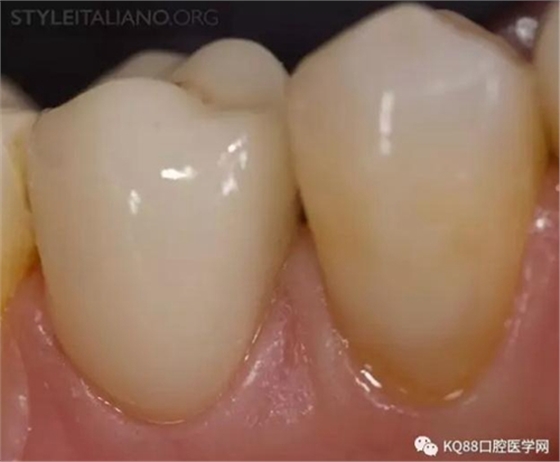

Img. 9 - Case 4: Another common cause of pain after a completed endodontic treatment is tooth fracture. This adverse event is most likely to occur if a restoration with cuspal coverage is not provided. Thereafter, waiting for the complete healing of an endodontic lesion prior to perform cusp coverage is dangerous.

Img. 10 - A crown-root fracture occurred while waiting for complete healing of periapical lesion.

Img. 11 - Luckily, this case was still restorable, despite a minor loss of attachment.

Img. 12 - A full ceramic crown provides function, aesthetics and a ferrule effect, so it was chosen as the best option for this case.